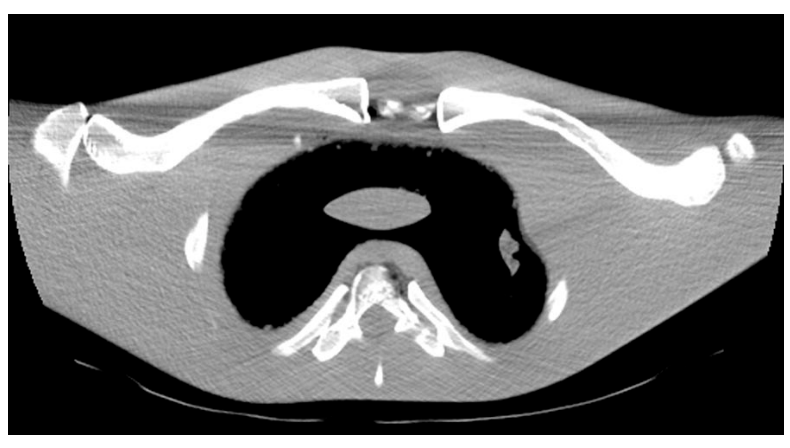

What is this artifact? How do we fix it?